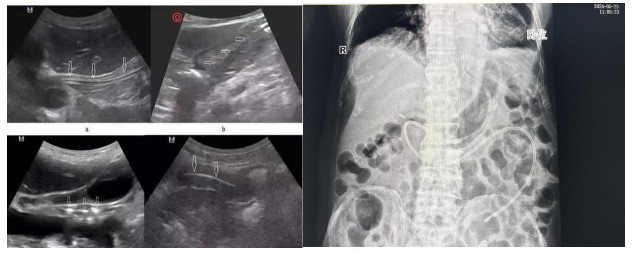

通訊員陽(yáng)琦珂報(bào)道:近日,83歲高齡的李爺爺因“重癥肺炎、呼吸衰竭”入住衡陽(yáng)市中心醫(yī)院重癥醫(yī)學(xué)二科。李爺爺意識(shí)為昏睡狀,經(jīng)氣管切開后長(zhǎng)期不能經(jīng)口進(jìn)食,為有效解決李爺爺營(yíng)養(yǎng)保障這一大難題,科室主任劉洋、護(hù)士長(zhǎng)肖芳共同為患者進(jìn)行了整體、精準(zhǔn)的營(yíng)養(yǎng)評(píng)估,考慮到患者高齡且基礎(chǔ)疾病較多,經(jīng)過(guò)細(xì)致的床旁體查,認(rèn)為患者符合鼻空腸管的置入條件,在排除操作禁忌癥后,主管護(hù)師黃云在床旁B超引導(dǎo)下成功為李爺爺進(jìn)行鼻空腸管置入術(shù)。

經(jīng)腹部X片驗(yàn)證一個(gè)完美的大“C”呈現(xiàn)出來(lái),確認(rèn)鼻空腸管已經(jīng)達(dá)到指定位置。

B超引導(dǎo)下營(yíng)養(yǎng)管置入術(shù)相比內(nèi)鏡輔助下營(yíng)養(yǎng)管置入,通過(guò)二維顯像觀察鼻腸管的位置,無(wú)創(chuàng)監(jiān)測(cè),定位準(zhǔn)確,提高了置管的成功率,能有效減少置管給病人帶來(lái)的不適體驗(yàn)及不必要的損傷。營(yíng)養(yǎng)支持已成為重癥患者綜合治療重要環(huán)節(jié),對(duì)重癥患者預(yù)后起著關(guān)鍵作用,新喂養(yǎng)途徑的建立,讓腸內(nèi)營(yíng)養(yǎng)支持順利的開展,不僅減少了患者的痛苦,也為重癥營(yíng)養(yǎng)支持治療開辟了一條嶄新的補(bǔ)給通道。